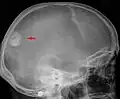

-

Meningeom im Röntgenbild des Schädels -